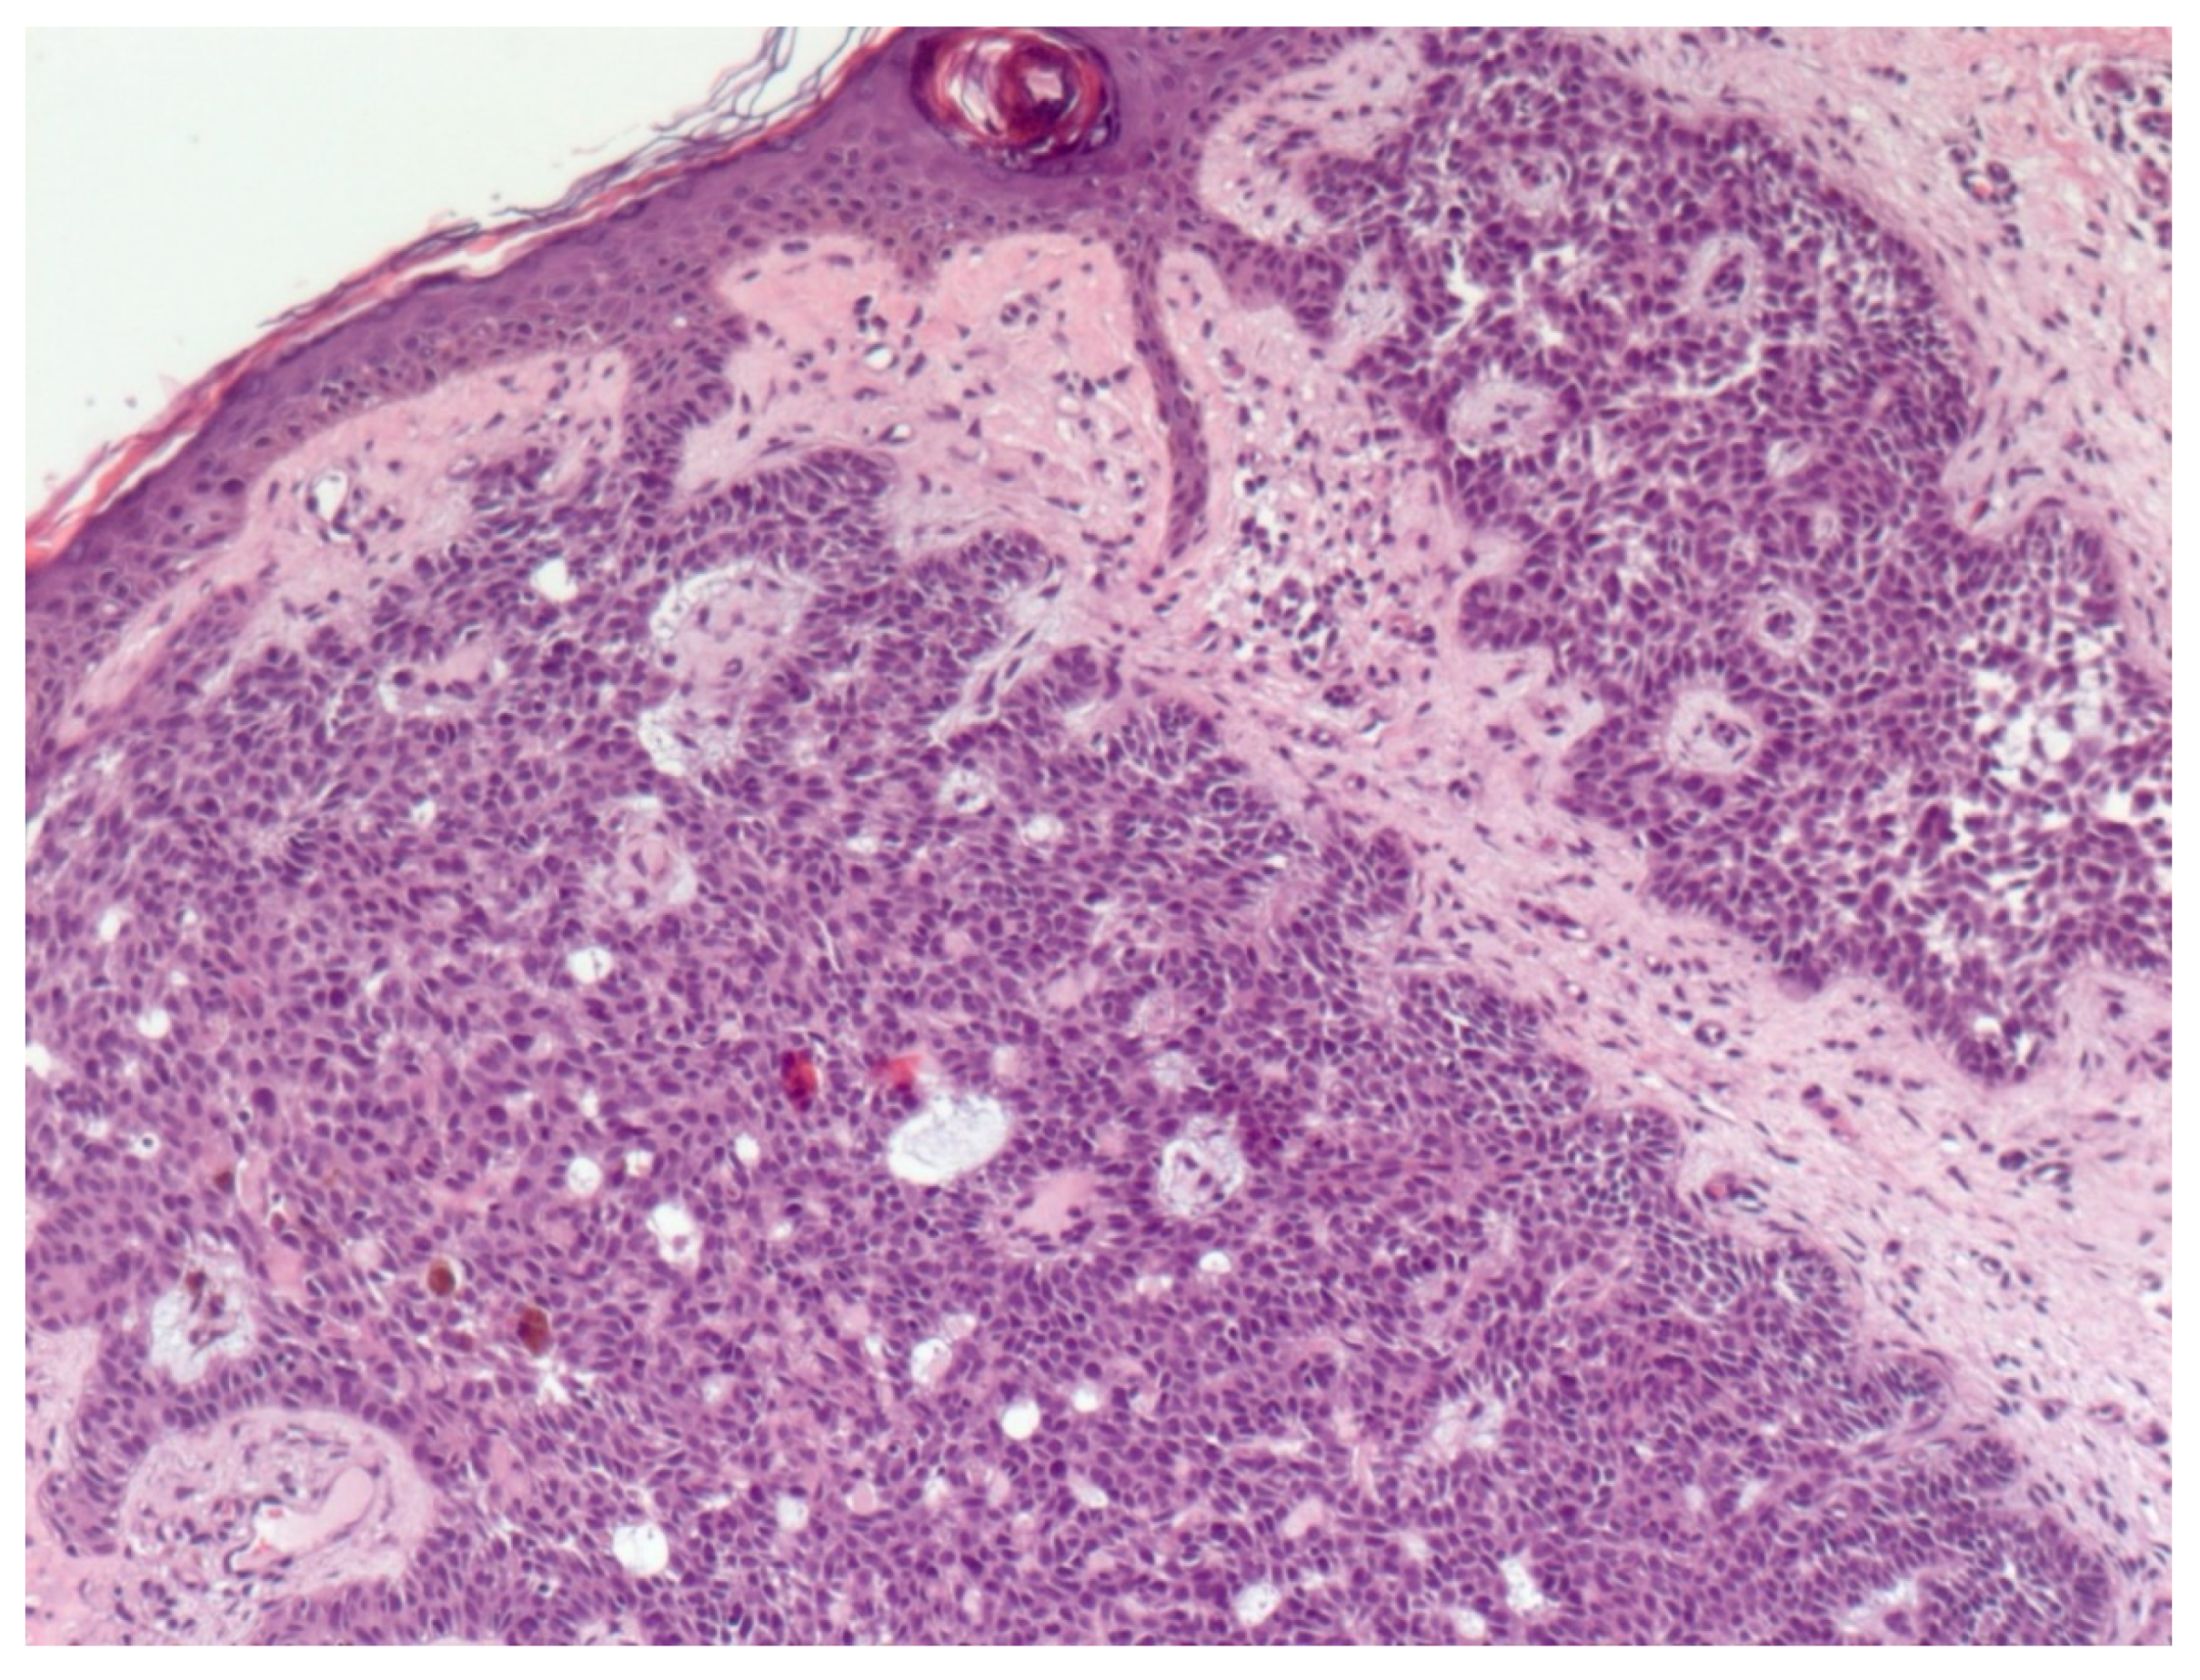

4. Histopathological Features of BCC

- Paolino, G.; Donati, M.; Didona, D.; Mercuri, S.R.; Cantisani, C. Histology of Non-Melanoma Skin Cancers: An Update. Biomedicines 2017, 5, 71. [Google Scholar] [CrossRef]

- Crowson, A.N. Basal cell carcinoma: Biology, morphology and clinical implications. Mod. Pathol. 2006, 19 (Suppl. 2), S127–S147. [Google Scholar] [CrossRef] [PubMed]